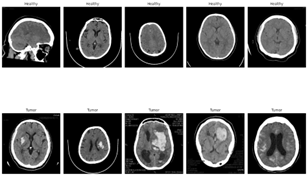

Refer to caption

Figure 2: Brain Tumor Dataset Images